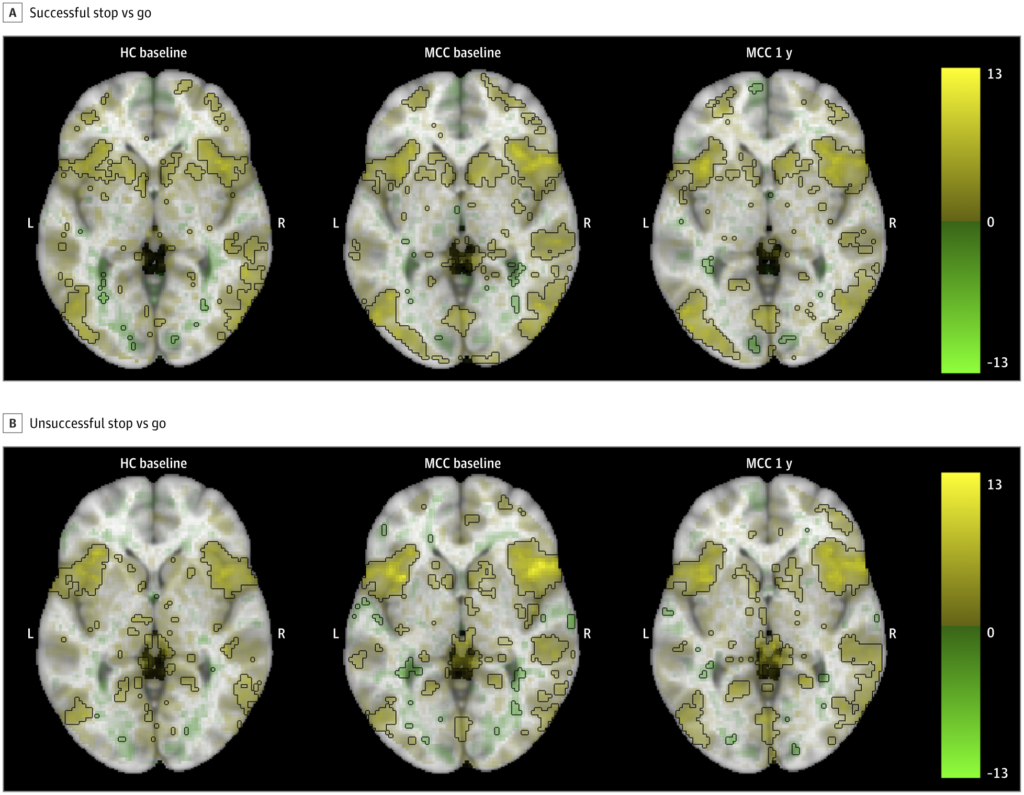

Study: Year-Long Medical Marijuana Use Shows No Negative Impact on Brain Function

According to a study published recently in JAMA Network Open, there was no significant impact on brain activation in individuals using medical marijuana over the course of a year. Titled Year-Long Cannabis Use for Medical Symptoms and Brain Activation During Cognitive Processes and conducted by researchers from Universitas Mercatorum, University of Foggia, University of Bari, and …